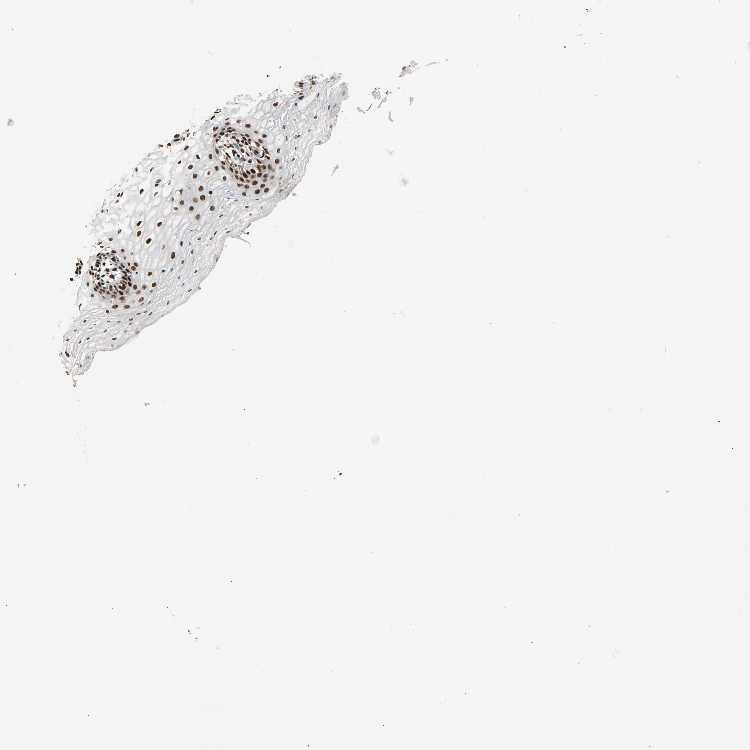

VAGINA - Antibody stainingi

Antibody staining in the annotated cell types in the current human tissue is reported as not detected, low, medium, or high, based on conventional immunohistochemistry profiling in selected tissues. This score is based on the combination of the staining intensity and fraction of stained cells.

Each image is clickable and will lead to virtual microscopy that enables deeper exploration of all samples and also displays staining intensity scores, fraction scores and subcellular localization as well as patient and tissue information for each sample.

Antibody HPA007484

Squamous epithelial cells High